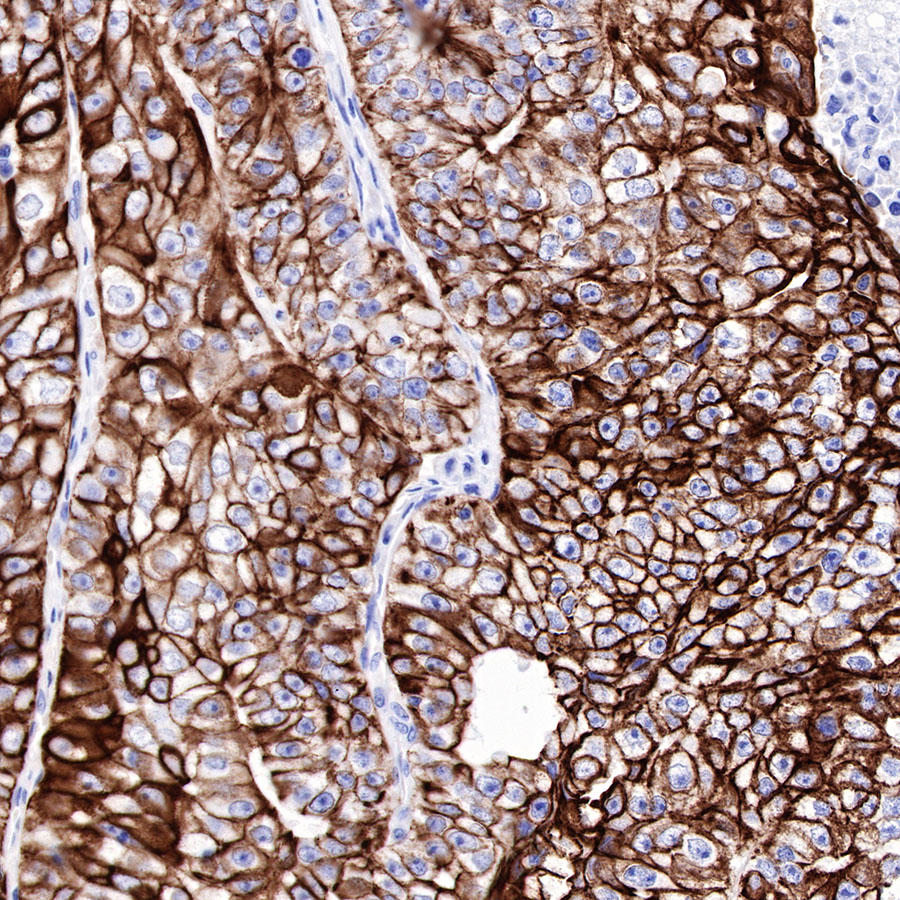

Background

| IHC-P |

1:500-1:2000 |